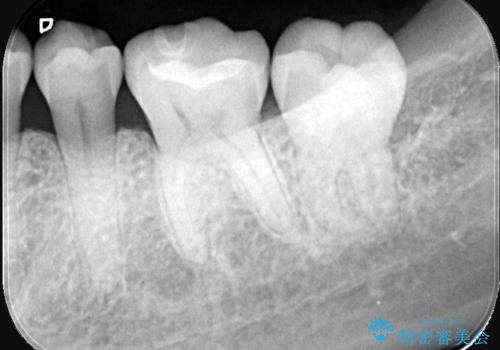

歯が欠けたことによるものか、もしくは以前装着された修復物の不適合が原因と考えられますが、銀歯(メタルインレー)と歯との間に大きな段差が認められ、汚れが溜まりやすい状態となっていました。

このような状態では、修復物の内部で虫歯が進行している可能性が高いため、治療が必要と判断しました。